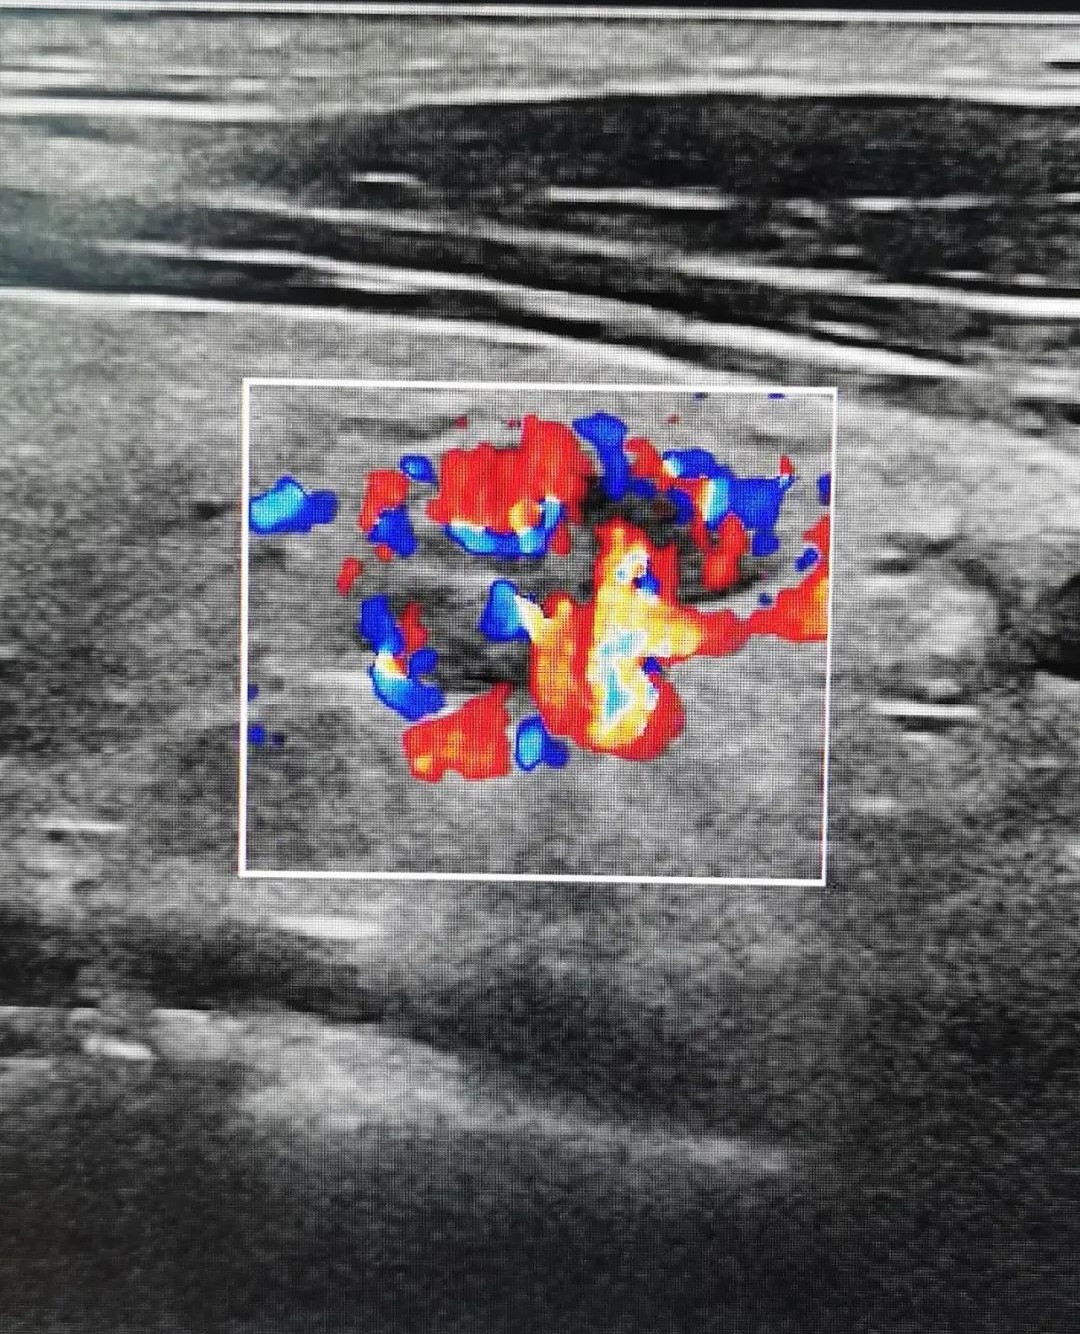

粤美特医疗健康体检中心从美国GE公司引进的目前彩超领域最先进的冰晶全“芯”超声影像设备,具备全球首创的血流显示技术,在MVI超微细血流成像、血管类造影成像和Radiantflow立体血流成像等方面引领世界,全方位、多维度显示血流灌注信息,帮助临床医生迅速成为具备火眼金睛、识别早癌妖魔的“肿瘤早筛孙悟空”。

在近期粤美特公司内部的一次关爱员工健康体检中,具备丰富临床经验、来自三甲医院超声科的陶枫主任运用美国GE冰晶超声影像设备,通过观察血流显示和结节形态,快速检查出一位员工长有1cm的甲状腺瘤,并给出了“高度疑似恶性中期甲状腺癌”的超声检查意见,后经北大医院穿刺活检证实了陶主任的判断是完全正确的,目前患者正在北大深圳医院住院手术治疗。

▲被查出的直径1cm恶性甲状腺瘤的立体血流成像图